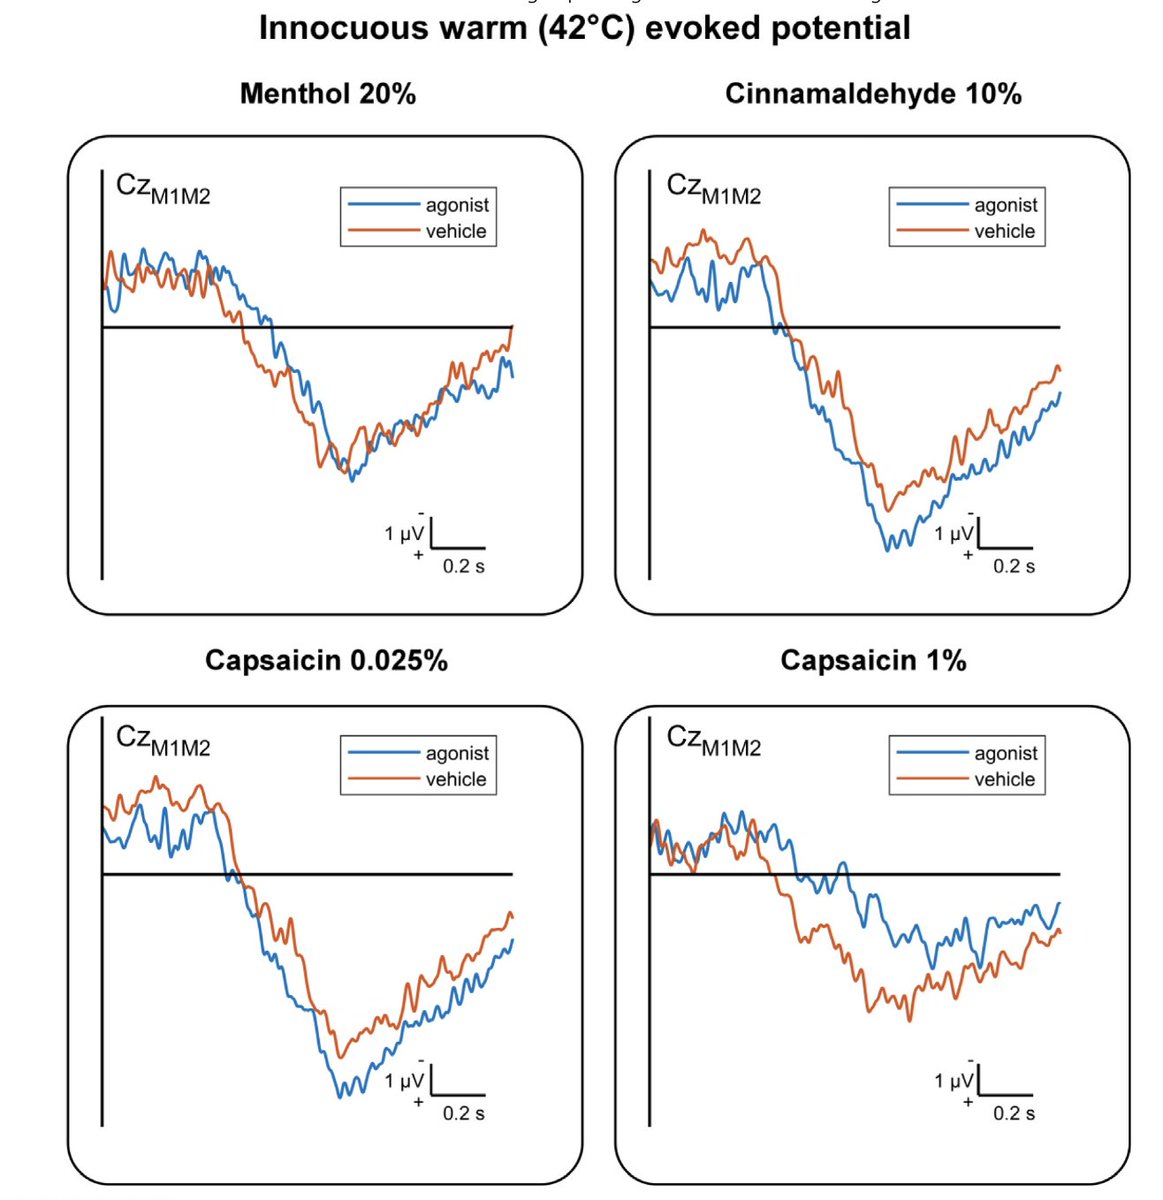

"Combining Topical Agonists With the Recording of Event-Related Brain Potentials to Probe the Functional Involvement of TRPM8, TRPA1 and TRPV1 in Heat and Cold Transduction in the Human Skin", by @arthur_courtin and André Mouraux is now out! sciencedirect.com/science/articl…